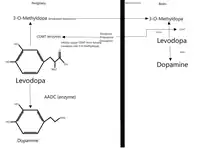

Levodopa

Levodopa is usually the first drug of choice when treating Parkinson's disease and has been the most widely used PD treatment since the 1980s.[105][111] The motor symptoms of PD are the result of reduced dopamine production in the brain's basal ganglia. Dopamine fails to cross the blood–brain barrier so it cannot be taken as a medicine to boost the brain's depleted levels of dopamine. A precursor of dopamine, levodopa, can pass through to the brain where it is readily converted to dopamine. Administration of levodopa temporarily diminishes the motor symptoms of PD.

Only 5–10% of levodopa crosses the blood–brain barrier. Much of the remainder is metabolized to dopamine elsewhere in the body, causing a variety of side-effects, including nausea, vomiting, and orthostatic hypotension.[112] Carbidopa and benserazide are dopa decarboxylase inhibitors that fail to cross the blood–brain barrier and inhibit the conversion of levodopa to dopamine outside the brain, reducing side-effects and improving the availability of levodopa for passage into the brain. One of these drugs is usually taken along with levodopa and is available combined with levodopa in the same pill.[113]

COMT inhibitors

During the course of PD, affected people can experience a wearing-off phenomenon, where a recurrence of symptoms occurs after a dose of levodopa, but right before their next dose.[69] Catechol-O-methyltransferase (COMT) is a protein that degrades levodopa before it can cross the blood–brain barrier and COMT inhibitors allow for more levodopa to cross.[119] They are normally used in the management of later symptoms, but can be used in conjunction with levodopa/carbidopa when a person is experiencing the wearing off-phenomenon with their motor symptoms.[69][111]